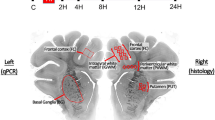

Following baseline recordings and surgery, piglets received a 2 µg/kg LPS bolus, followed by 1 µg/kg/h LPS infusion continued for 52 h. After 4 h of infusion, piglets underwent a transient hypoxic–ischemic (HI) insult. Animals were subsequently randomized to (i) normothermia (NT, core 38.0–39.0 °C throughout) or (ii) hypothermia (HT, 33.5 °C from 1 to 25 h post HI, then rewarmed at 0.5 °C/h). Blood samples were collected at baseline, 4 h after bolus, end HI (time 0), and at 3, 12, 24, and 48 h after HI. EEG was continuously acquired, excluding during MRS at 24 and 48 h. Piglets were maintained under meticulous intensive care for 48 h following HI, prior to euthanasia and histological specimen collection.

Brain histology

Forty-eight hours after HI, piglets were euthanized and histological brain specimens were obtained and prepared as previously described.10 Cell death was quantified by nuclear DNA fragmentation using histochemistry with TUNEL. Glial activation was quantified using the presence of astrocyte glial fibrillary acidic protein (GFAP) and microglial ionized calcium-binding adaptor molecule 1 (IBA1) immunoreactivity. Cleaved caspase-3 (CC3) immunoreactivity was quantified. Histological analysis was performed by investigators blind to the treatment group. Eight brain regions were assessed (cingulate cortex, sensorimotor cortex, hippocampus, periventricular white matter, internal capsule, caudate nucleus, putamen, and thalamus). For each region, TUNEL-positive nuclei were counted in six fields (three per section, at ×40 magnification, with an area of 0.066 mm2) and the average converted into counts per mm2. IBA1-positive cell body count was similarly performed. In addition, IBA1 ramification index was calculated in six fields per region, at ×40 magnification, using a 0.049 mm × 0.049 mm square grid. The microglial ramification index was calculated as (B2/C), where C is the number of cell bodies within the grid, and B is the number of branches crossing the three horizontal and three vertical gridlines. CC3 immunoreactive cells were counted in four fields per region (at ×20 magnification with an area of 0.164 mm2) and the average converted into counts per mm2. To quantify the GFAP immunoreactivity optical luminosity values were calculated by deducting mean brightness values of the tissue (four fields per region at ×20 magnification) from the mean brightness of the blank slide.